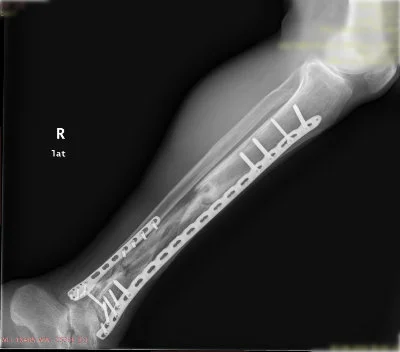

Görüntüleri büyütmek için resmin üstüne tıklayınız.